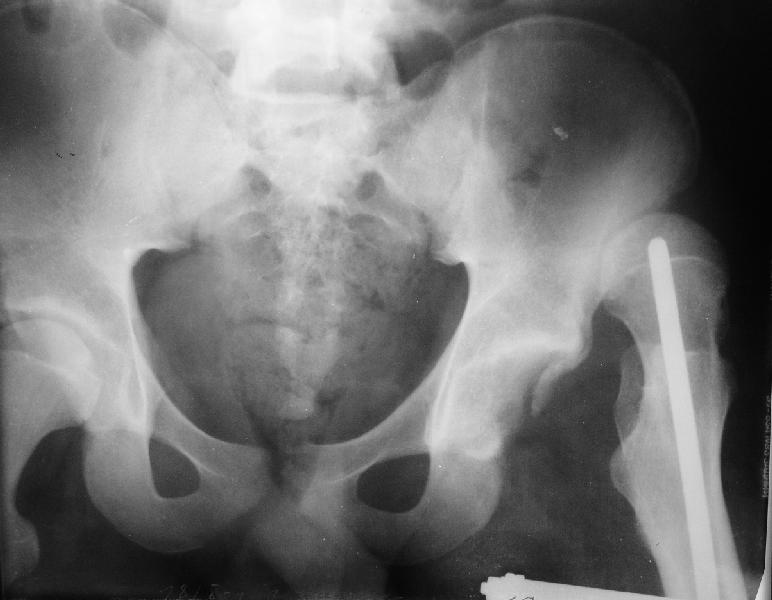

Уважаемые коллеги,пожалуйста, подумайте над следующим ребусом. В нашу клинику поступилпациент из области, 17лет, получивший травму в ДТП 25.08.04, открытый перелом бедра, при поступлении наложено скелетное вытяжение.

30.09.04 на операции выявлен вывих бедра и перелом голени на этой же стороне. Остесинтез бедра все же выполнен, и по заживлении раны пациент переведен к нам. Кроме того у пациента нейропатия седалищного нерва на этой же стороне. В нашей клинике планируется наложение аппарата таз-бедро, для постепенного низведения бедра с последующим открытым вправлением, замена фиксатора на запираемый гвоздь и блокируемый остесинтез голени. Вариант с первичным эндопротезированием мы не рассматривали из-за юного возраста пациента. Вопрос с чего начать? Кроме того, сгибание в коленном суставе в настоящее время (95 градусов) затрудняет остеосинтез голени.Стоит-ли менять гвоздь? Или же спилить торчащий конец во время открытого вправления? Может, попробовать все сделать одномоментно? Заранее спасибо.

На мой взгляд, на ренгенограмме таза (левый сустав) имеется (имелось) перелом заднего края вертлужной впадины, перелом ацетабулум-вывих головки? (нужны дополнительные снимки).

если проследить две линии: передний и задние края ацетабулум должны встречатmся с латеральной стороны ацетабулум, а у данного больного они формирует цифру "8", т.е. передний край ацетабулум расположен более спереди. Ацетабулум у этого больного немного в ретроверсии, т.е. задний край у него недоразвит и трудно удержать головку в cуставе после реконструкции.

Больной нуждается в дополнительных исследованиях: Ренгенограмму таза, Judet view левого сустава, бедро, голень и КТ ацетабулум. После этих данных можно подумать над этим ребусом, хотя согласен с

мнениями о физиологической низведении головки аппаратом, в этом случаи считаю метод Илизарова идеальным и надо начать сразу же.